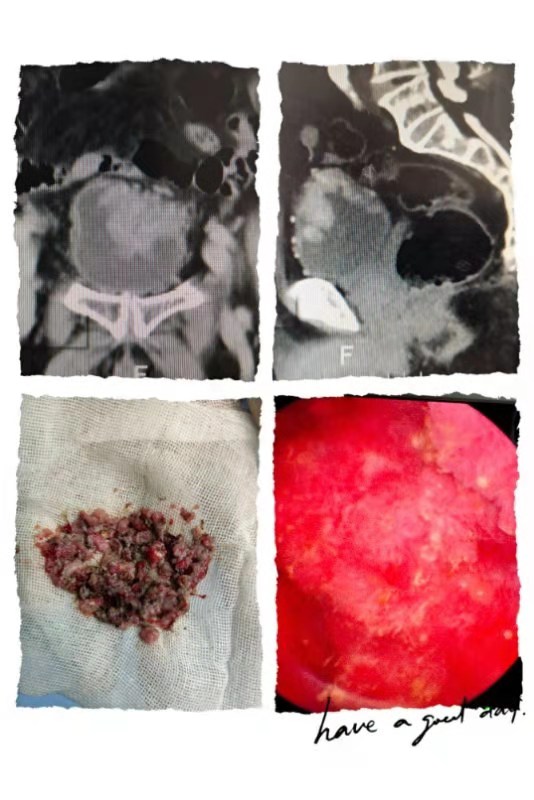

87岁老年男性,发现肉眼血尿一周,在其他医院检查怀疑膀胱占位。经多方打听到郑州市第九人民医院进一步诊治:增强CT提示膀胱占位,考虑膀胱癌。6月1日上午行经尿道膀胱肿瘤电切术,发现膀胱内肿瘤长满大半个膀胱,而且基底部宽大没有明显界限。